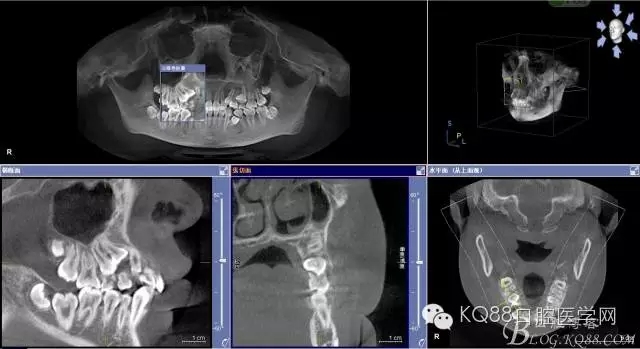

圖2.術(shù)前cbct檢查:54、55乳牙滯留,14、15埋伏阻生,14位于15的上方。

圖4.從局部影像,可以看出14牙冠位于15牙冠與13牙根之間。

圖5.水平剖面觀:14牙冠緊鄰15與13牙根之間,要求分牙一定要小心謹(jǐn)慎